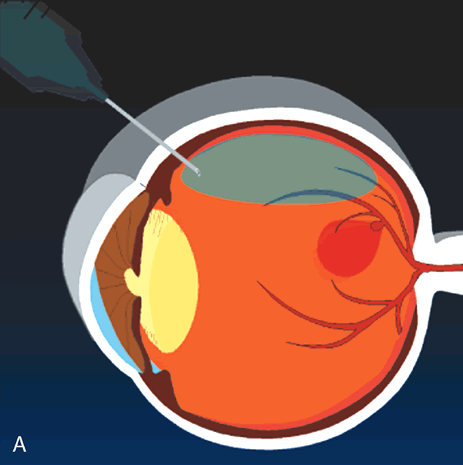

Nd-YAG laser photodisruption may be employed in special cases in which thick, fresh blood is trapped beneath the internal limiting membrane13 or behind the posterior hyaloid.14 Blood in these anatomic locations does not itself cause damage to the retina, but it may limit central vision, and it may prevent the clinician from identifying underlying retinal pathology. Photodisruption results in a localized concussive effect that breaks open the posterior hyaloid or internal limiting membrane. If the trapped blood has not yet solidified, it may then be allowed to “spill out” through the opening into the vitreous cavity (Fig. 5). Risks of this technique include damage to the underlying retina if the laser treatment is applied too close to the retina or if the blood is not thick enough to absorb the concussive effect.

Fig. 5. A. Illustration of a macroaneurysm with thick sub-internal limiting membrane (ILM) hemorrhage Because the hemorrhage obscures the macula, the patient's visual acuity is poor and it is not possible to determine clinically if the hemorrhage extends beneath the macula. Nd-YAG laser photodisruption can break through the ILM. B. If the blood has not yet solidified, it may drain through the laser opening and improve visual acuity and visualization of the macula.